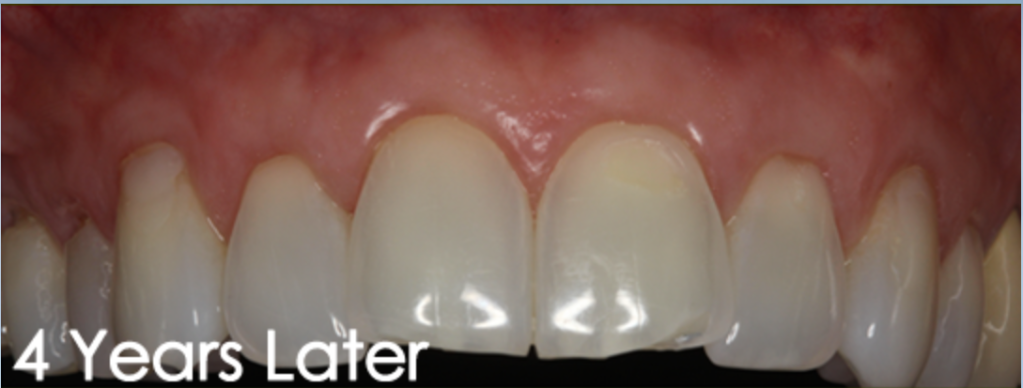

General Disclaimer: The results in the photographs are examples only and do not imply any certainty of the result of a procedure, and all outcomes are subject to the circumstances of the individual patient.

The Pinhole surgical technique also known as Pinhole gum rejuvenation is a scalpel free, graft free, and minimally invasive procedure for correcting gum recession and saving teeth. Through a small hole made by the needle, specially designed instruments are used to gently loosen the gum tissue and glide it over the receded part of the tooth. Patients can expect minimal post-operative symptoms such as pain, swelling, and bleeding. Patients are pleasantly surprised by the instant cosmetic improvement. Most patients are able to resume light normal activities within 24 to 48 hours after treatment excluding working out and strenuous activities.

General Disclaimer: The results in the photographs are examples only and do not imply any certainty of the result of a procedure, and all outcomes are subject to the circumstances of the individual patient.